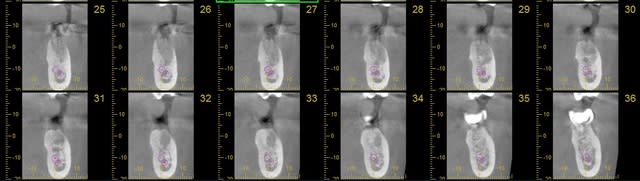

--- Pour la 36 :

Malgré la temporisation de un an, je trouve que la densité osseuse semble anormal au niveau du site d'extraction.

Vous qui avez plus de recul, pensez vous qu'il s'agit d'un os cicatrisé, juste moins dense, ou alors de vraies lacunes osseuses ?

Dans ce cas, moi qui pensait poser un 5x10mm, pensez vous que je doive envisager une greffe de comblement par biooss et membrane pendant la chirurgie, ou bien ouvrir, mettre l'os et la membrane et refermer pour attendre encore, ou bien que la pose de l'implant sera possible, sans os.

Scanner 36 no7szy - Eugenol